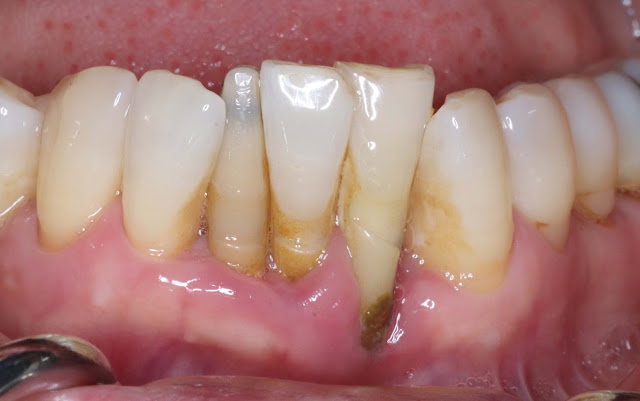

This is a 64-year-old female patient.

The condition of the lower anterior teeth is poor.